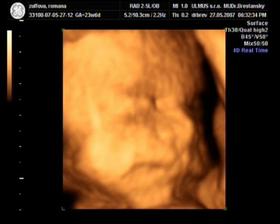

Nas pokladik Adamko

Asi presne na Vianoce 2006 sa nam podarilo stvorit maly zazrak, ktory bude snad pekne rast a robit nam radost 🙂

11.9. 2007 sa nam pokladik narodil a vola sa Adamko.